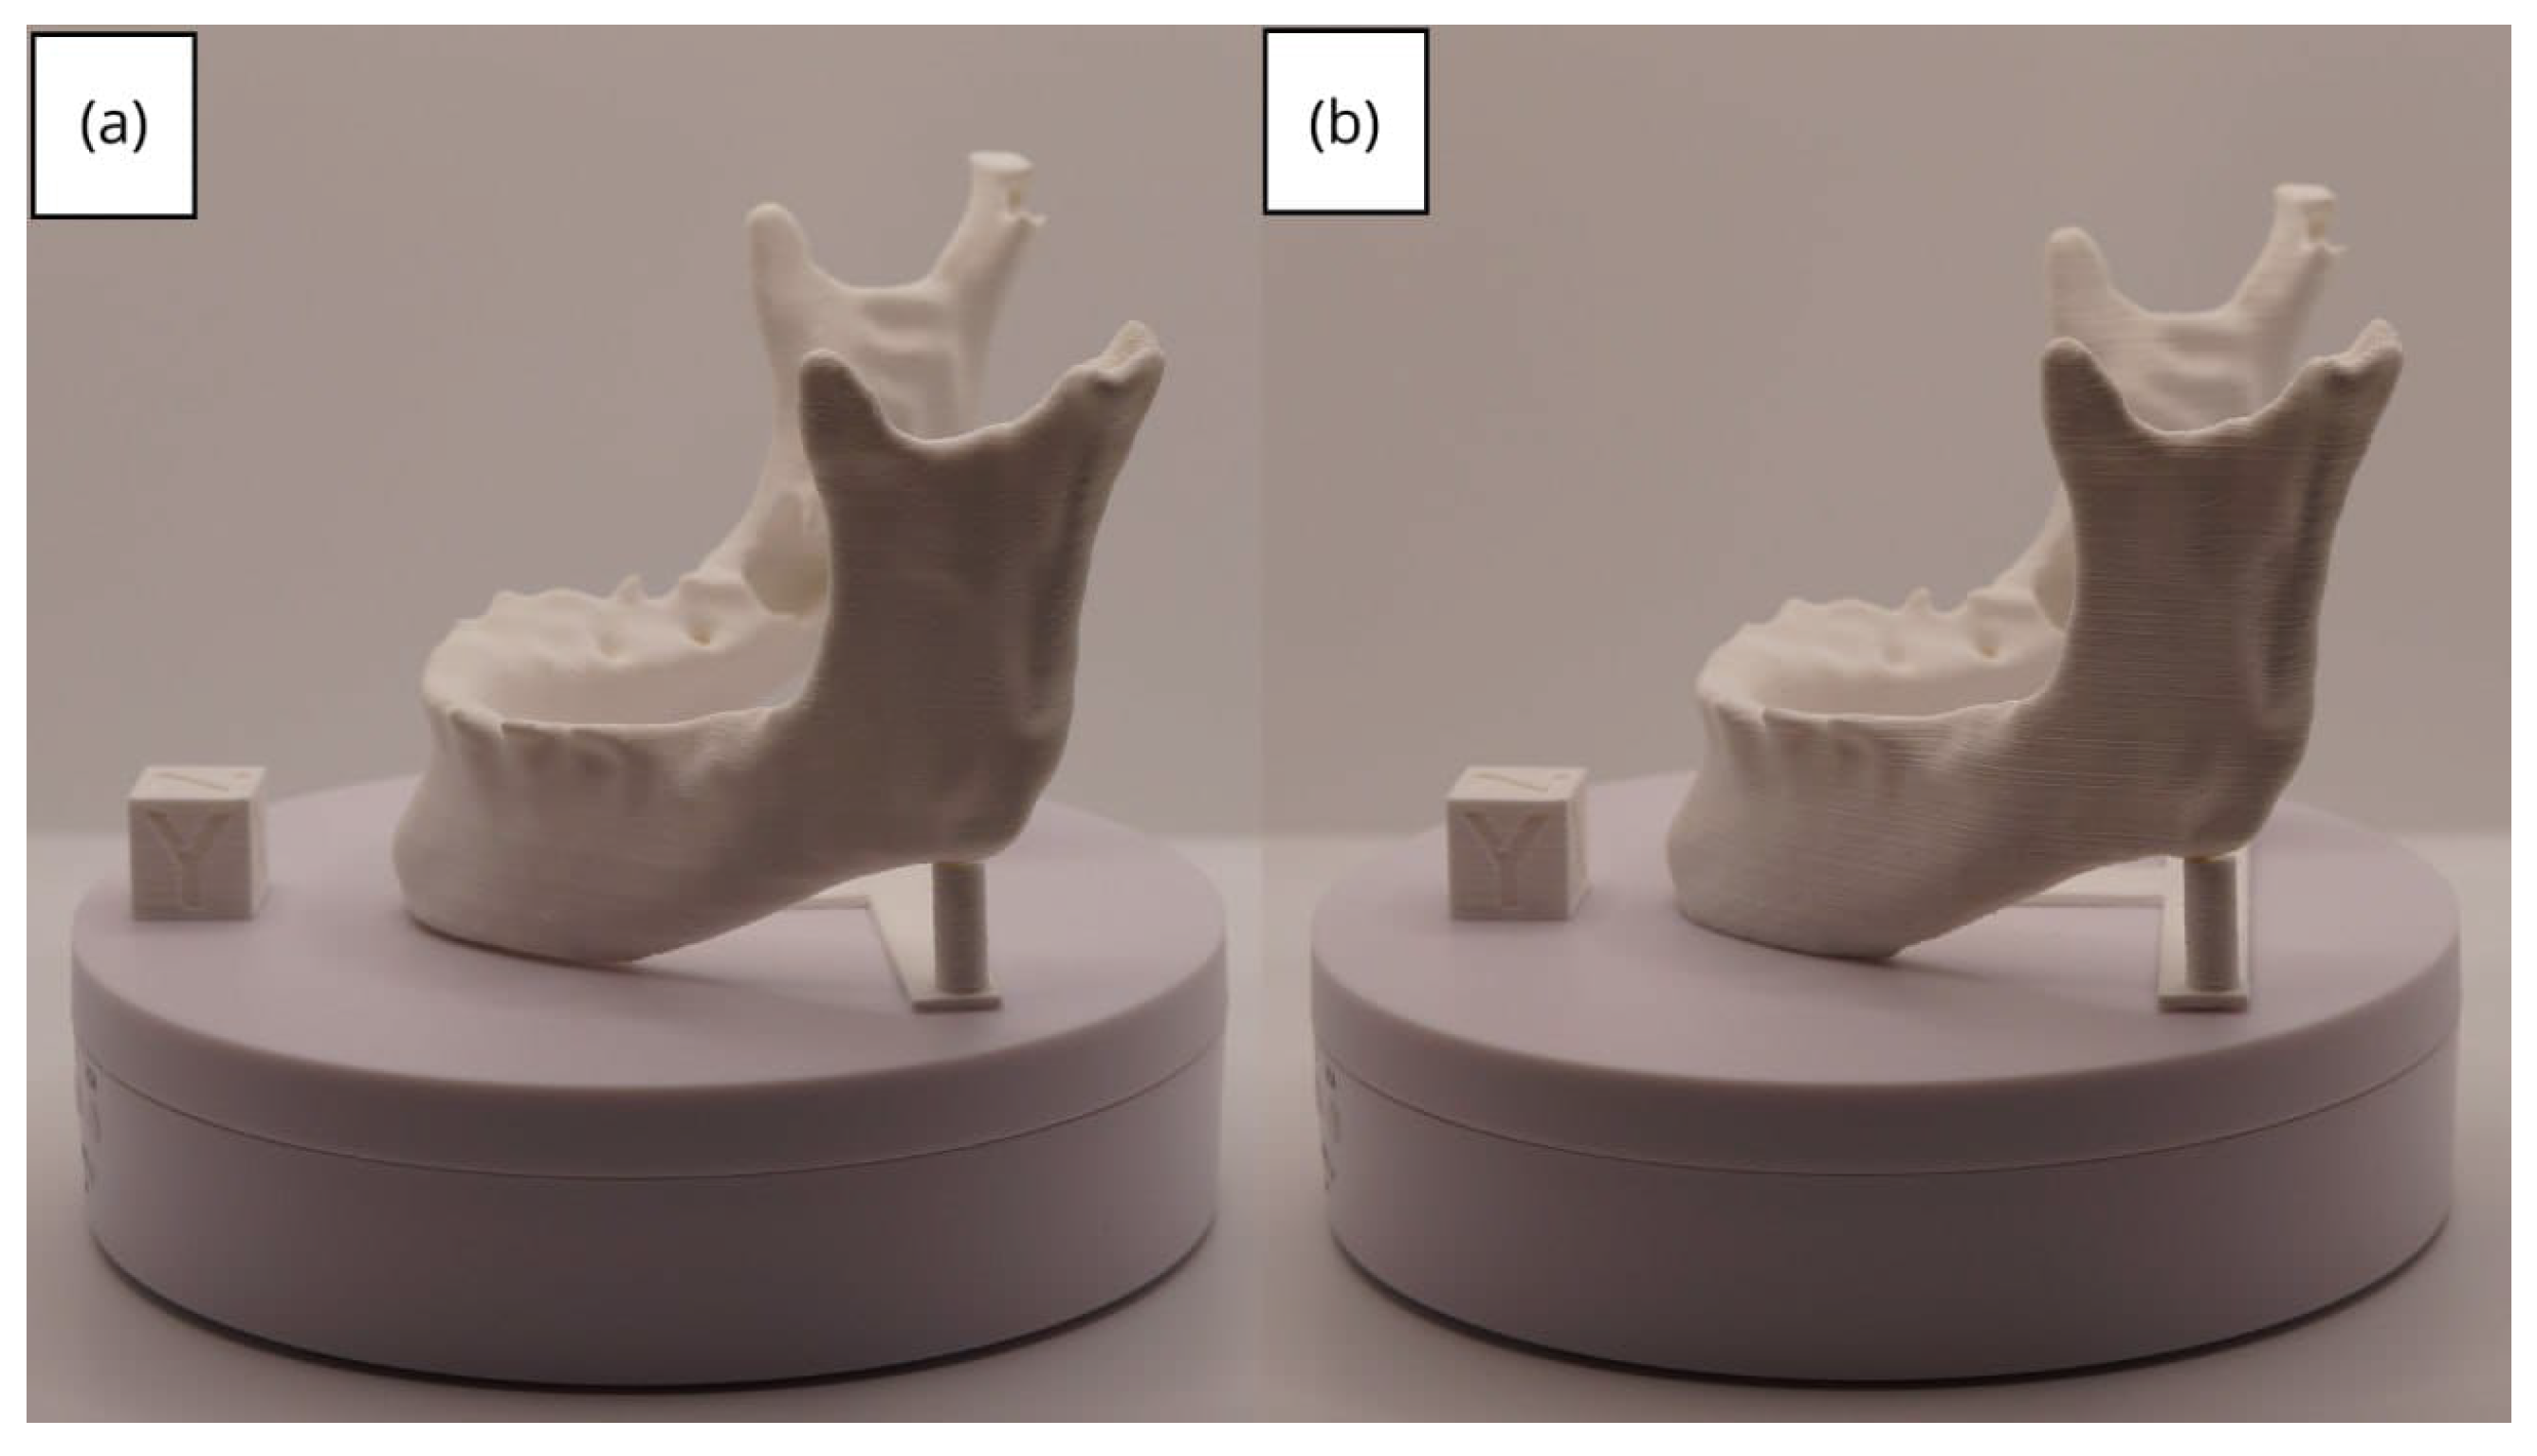

3.2. Human Lower Jaw

3.2.1. DICOM-to-STL Files

3.2.2. STL-to-GCODE Files

3.2.3. Final Printing

| Lower jaw models | m; m | Artillery Sidewinder X2 |

| m; m | Creality Ender 3 | |